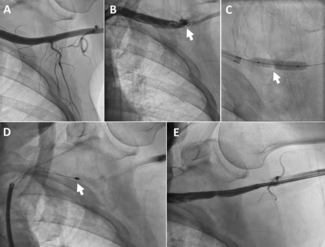

An 81-year-old woman with prior surgical aortic valve replacement presented with progressive dyspnea . Echocardiography showed severe bioprosthetic aortic stenosis with mild paravalvular leak and preserved ejection fraction.